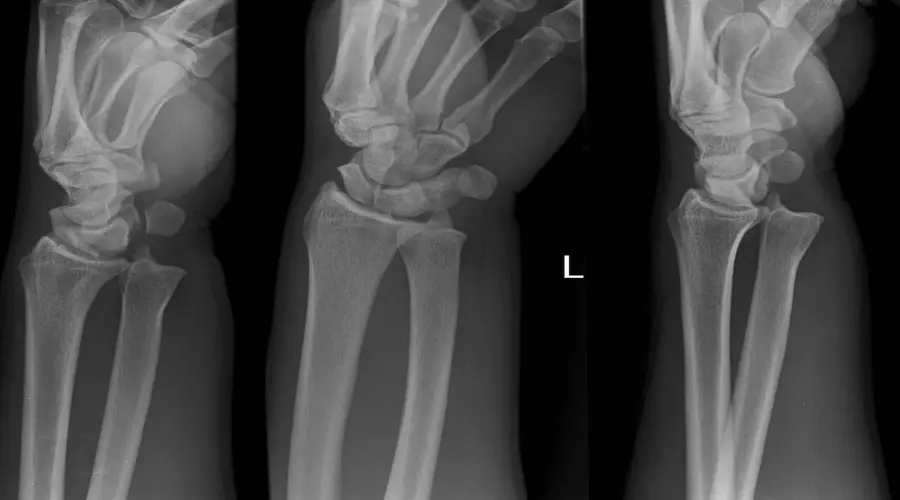

دررفتگی مچ دست 12 آذر 1402

• بیماری ها

• مقالات

دررفتگی مچ دست: علت‌ها، علائم و روش‌های درمان